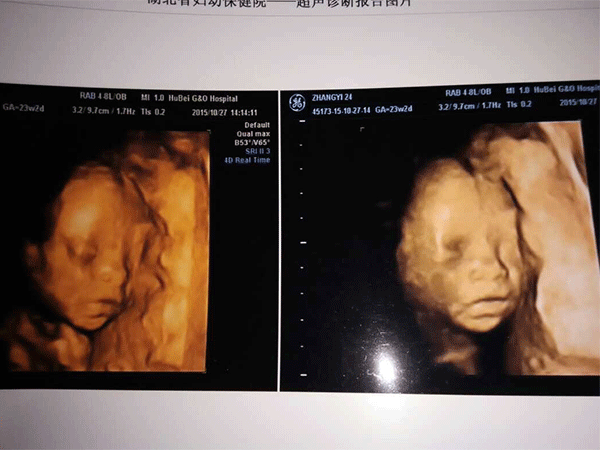

三维彩超,即彩色多普勒超声检查的一种,检查图像呈土黄色,通过多普勒超声仪器发出超声波,对体内各项器官进行成像。三维即其图像是立体的,可以更直观的看到器官的形态,及时发现病变并进行治疗。三维彩超常用于产检,用来判断胎儿的生长发育的情况或是否出现畸形等。

答案:三维彩超的检查时间是在22周-26周左右,其中,24周,也就是5-6个月去检查是最理想的。

24周的胎儿,其身体结构的生长发育已经很完善了,且胎儿大小也很合适,这时候做三维彩超可以很直观的看到胎儿的五官四肢、以及内脏器官,还能了解胎儿双顶径、头围、腹围、股骨长等发育情况。

不同孕周期宝宝的三维彩超各项参考值有所差异,不能根据一个孕周期的值去判断其他孕周期胎儿生长的情况。此外,三维彩超单上经常还会出现一些英文字母的缩写,其实,这些就是医生最常看的项目。

三维彩超常见英文字母代表:BDP--双顶径,AC--腹围,FL--股骨长,HL--肱骨长,AFI--羊水指数,HC--头围,HR--心跳次数,RI--胎儿的脐动脉阻力指数,S/D--收缩期/舒张期峰值比。